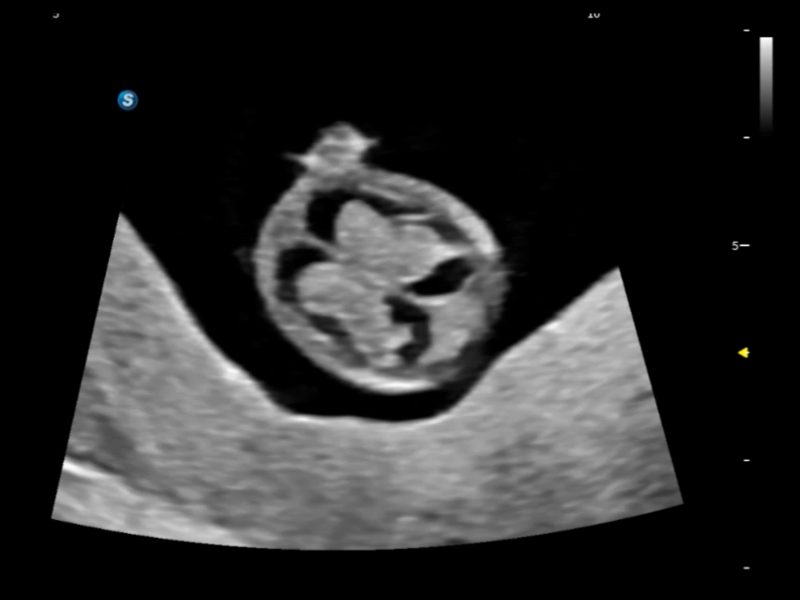

在傳統(tǒng)血流的基礎(chǔ)上優(yōu)化掃查和算法策略,能夠更好的抑制組織信息,提煉紅細(xì)胞運(yùn)動(dòng)信息,得到更高幀頻,高靈敏度和分辨率的血流信號(hào),還原更真實(shí)的血流動(dòng)力學(xué)。

通過(guò)光照模型,使二維血流顯示出立體的效果,增加血流的敏感性、成束性,減少外溢。可以和其他不同的血流技術(shù)聯(lián)合使用,融合不同技術(shù)的優(yōu)勢(shì)。輕松應(yīng)對(duì)微小血管,增強(qiáng)血流的立體效果,提升視覺(jué)敏感性。